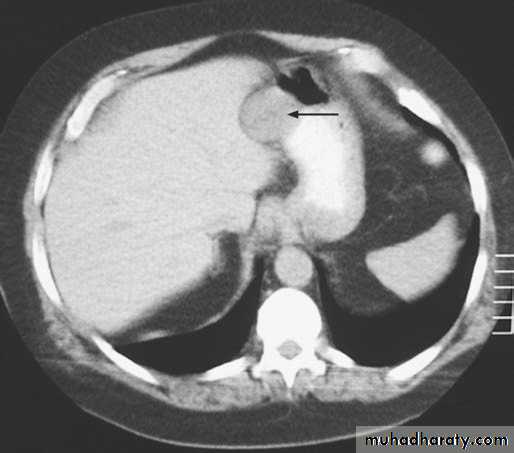

Computerised tomography scanning (CT Scan) and Magnetic resonant imaging.

1-DIRECT INVADE THE WALL THEN, LIVER, PANCREAS, COLON, OMENTUM.2-LYMPHATIC SPREAD BY PERMIATION & EMBOLIZATION.

3-BLOOD-BORNE METASTASIS.

4-TRANSPERITONEAL SPREAD.